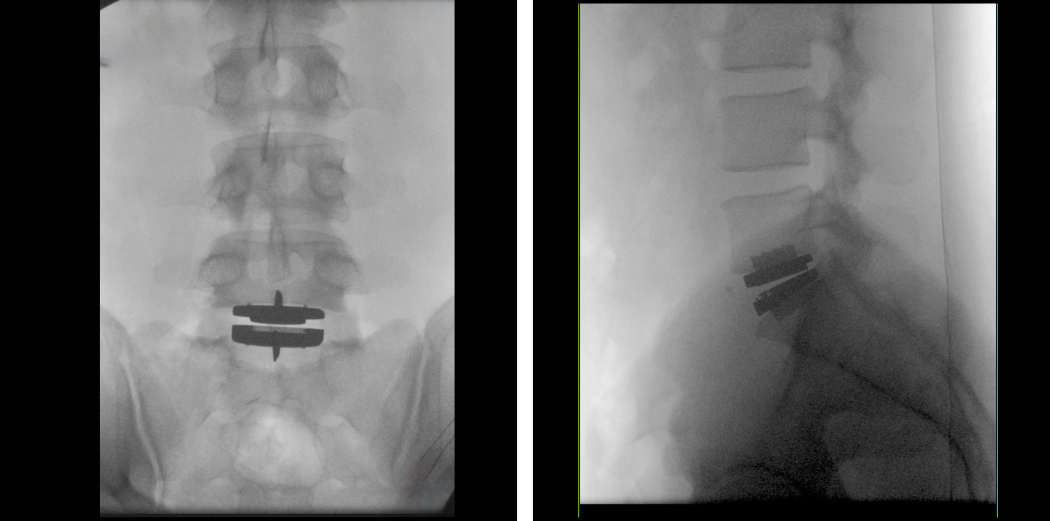

spine x-ray

The artificial disc is placed carefully, ensuring accurate positioning to maintain correct spinal alignment. After confirming everything is stable, Dr. Stieber closes the incision. Patients are typically encouraged to walk and engage in gentle movements within the first 24 to 48 hours, promoting circulation and reducing complications. A customized physical therapy plan helps guide your gradual return to normal activities over subsequent weeks and months.

prodisc L Surgical Technique